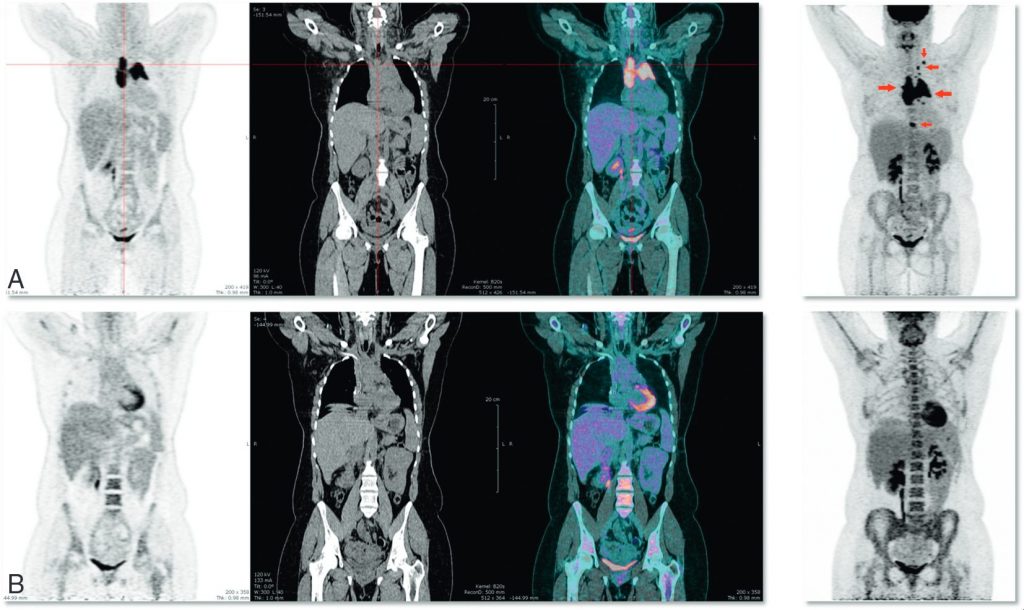

Fig. 94.4. TEP-TDM au 18FDG effectuée pour un lymphome de Hodgkin.

Bilan initial (A) : fixation du 18FDG au sein d’une masse médiastinale et de nœuds lymphatiques médiastinaux et supraclaviculaires gauches (flèches rouges). La TEP au 18FDG du même patient (B), effectuée en fin de protocole thérapeutique, n’objective plus d’anomalie de fixation dans les territoires initialement pathologiques, alors que la TDM montre la persistance d’une masse résiduelle. Le patient a été considéré en réponse complète en fin de traitement et n’a pas rechuté dans les cinq années qui ont suivi.

Source : CERF, CNEBMN, 2022.

De par sa capacité à caractériser les masses résiduelles, la TEP-TDM au 18FDG est recommandée lors de l’évaluation thérapeutique à mi-parcours des LH et LBDGC pour identifier les patients répondeurs des patients non répondeurs. La TEP au 18FDG est recommandée pour l’évaluation de fin de traitement des LH, LBDGC, LF et autres lymphomes avides de FDG, pour s’assurer de la réponse métabolique complète (figure 94.4).